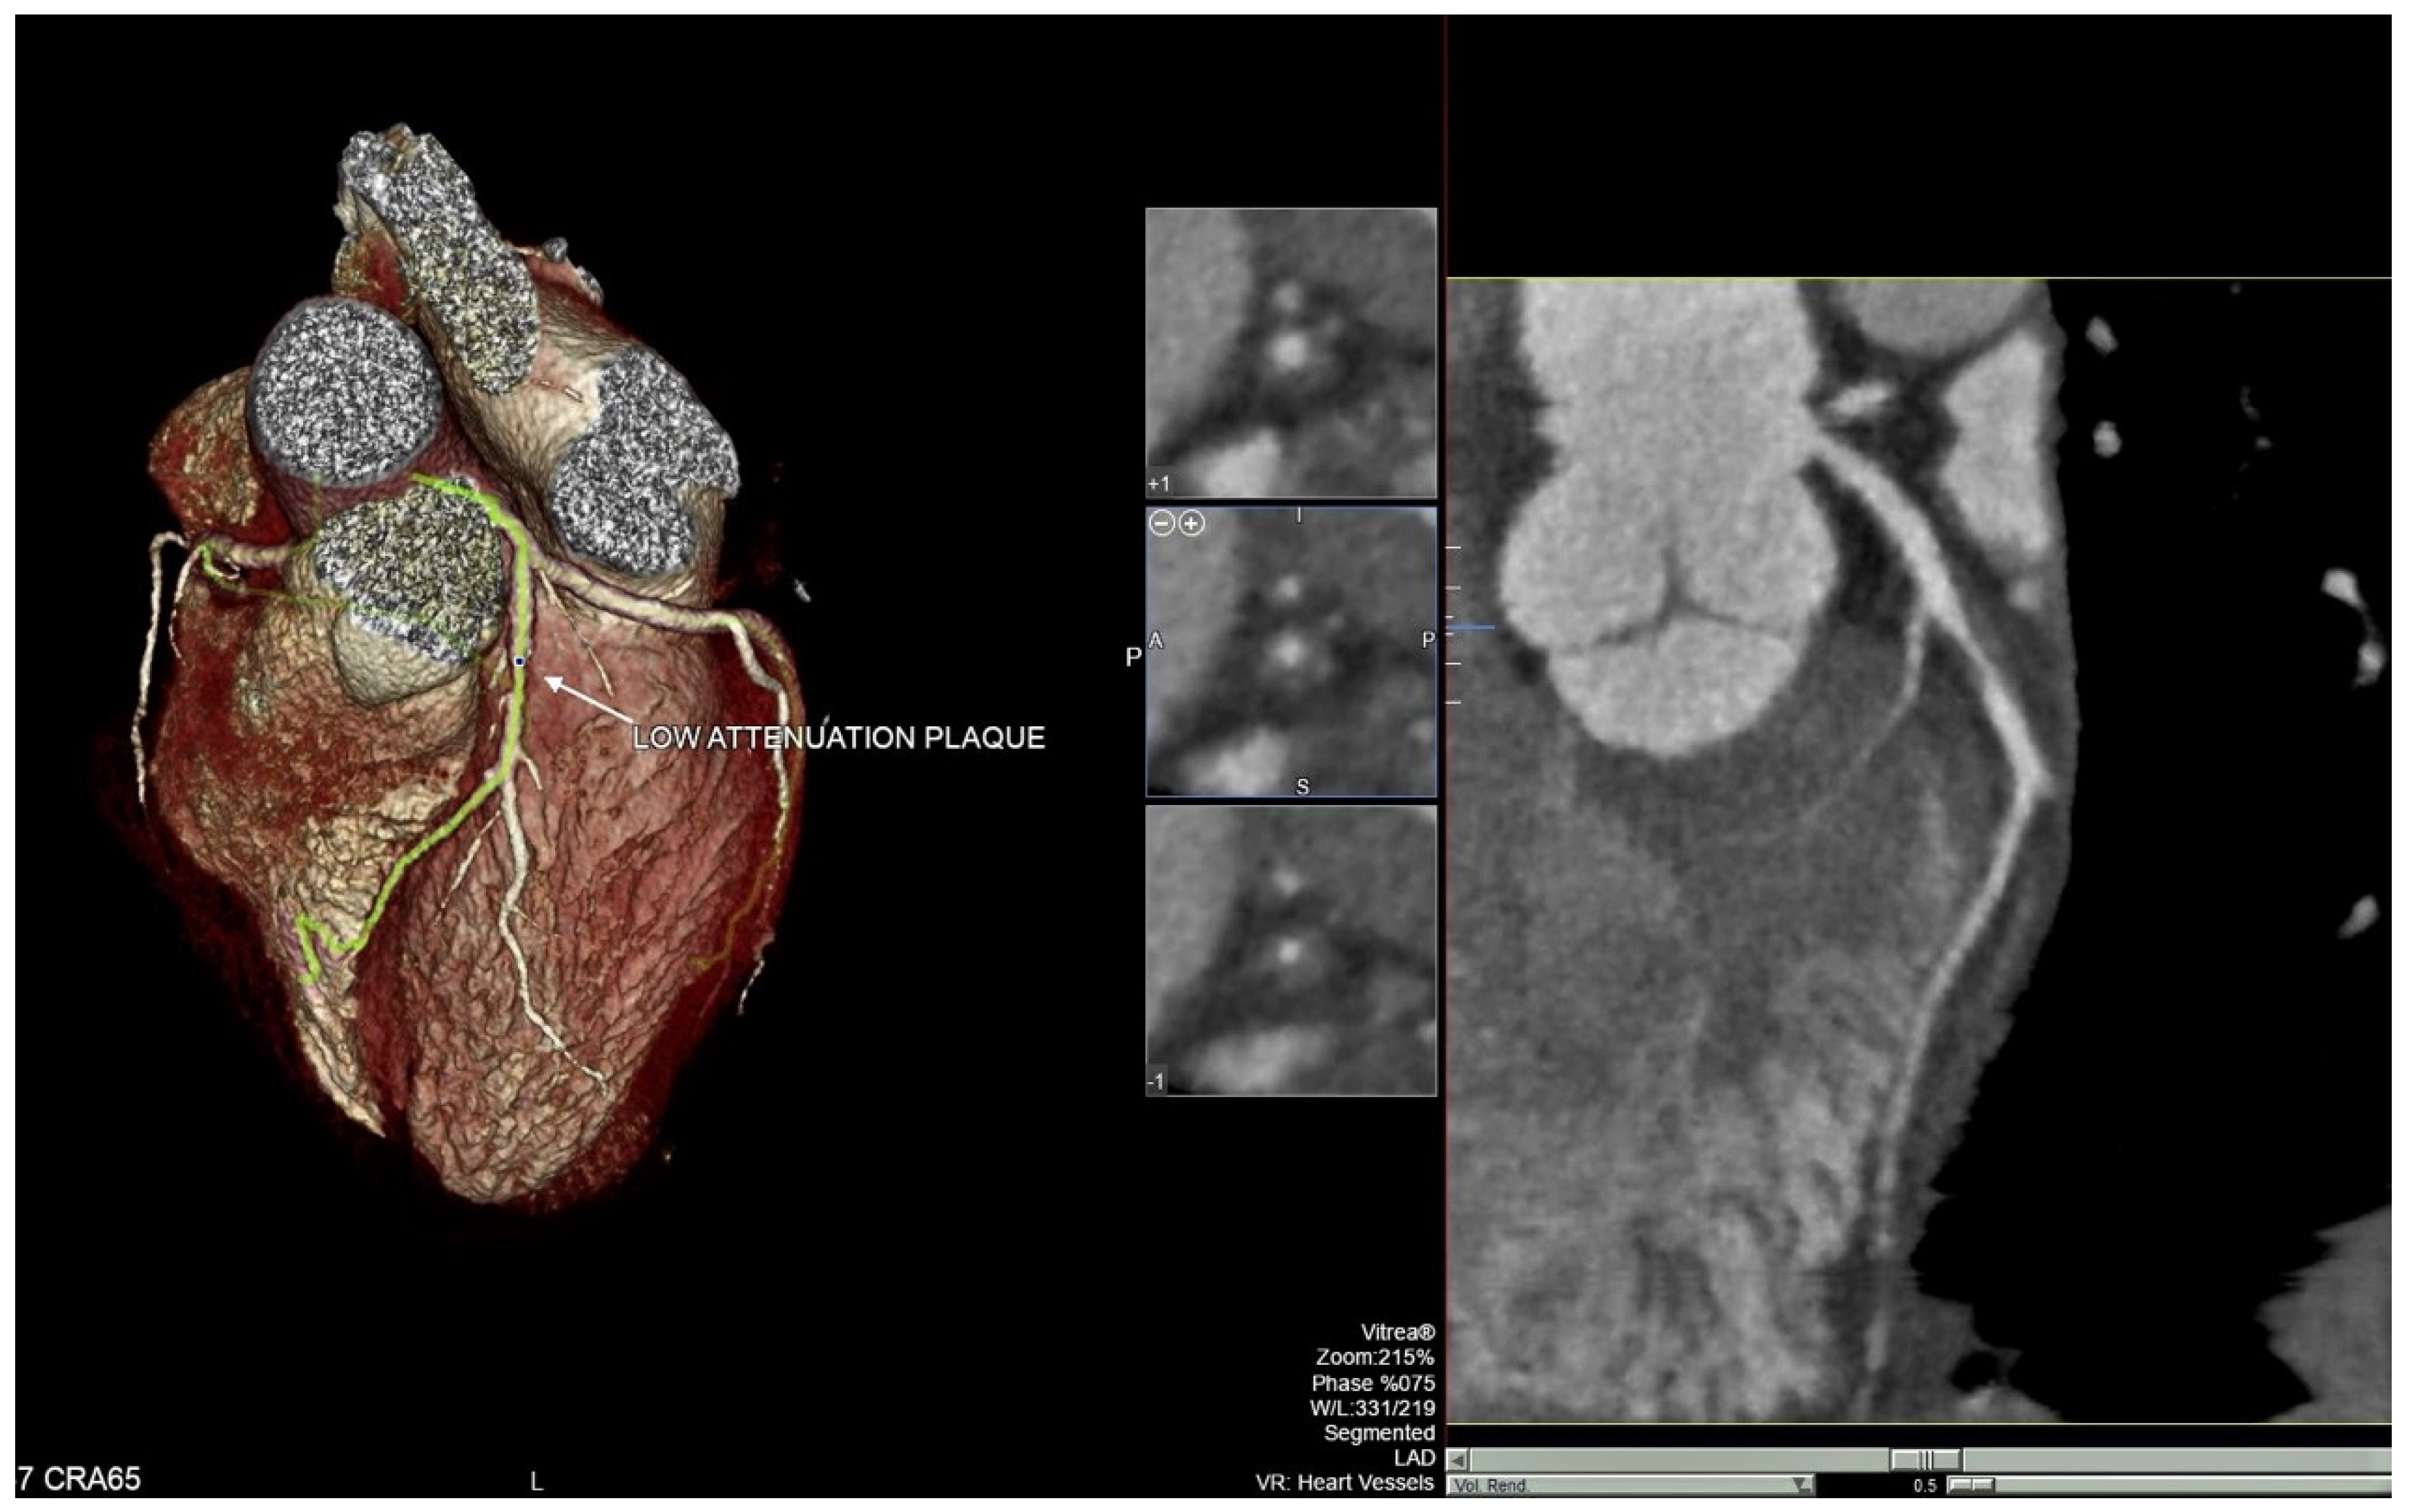

2.2. CCTA Technique

2.3. Pericoronary Fat Attenuation